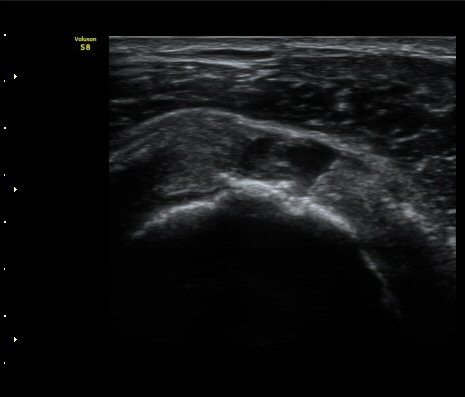

¿À±¸µ¹±â Ⱦ´Ü¸é°Ë»ç»ó ¿Áµ¹±â ¾Æ·¡, ³»Ãø, °ß°©ÇÏ±Ù°Ç Ç¥Ãþ¿¡¼­ ¼ö¾×Àú·ù°¡ °üÂûµÈ´Ù

(±×¸² 3, 4).